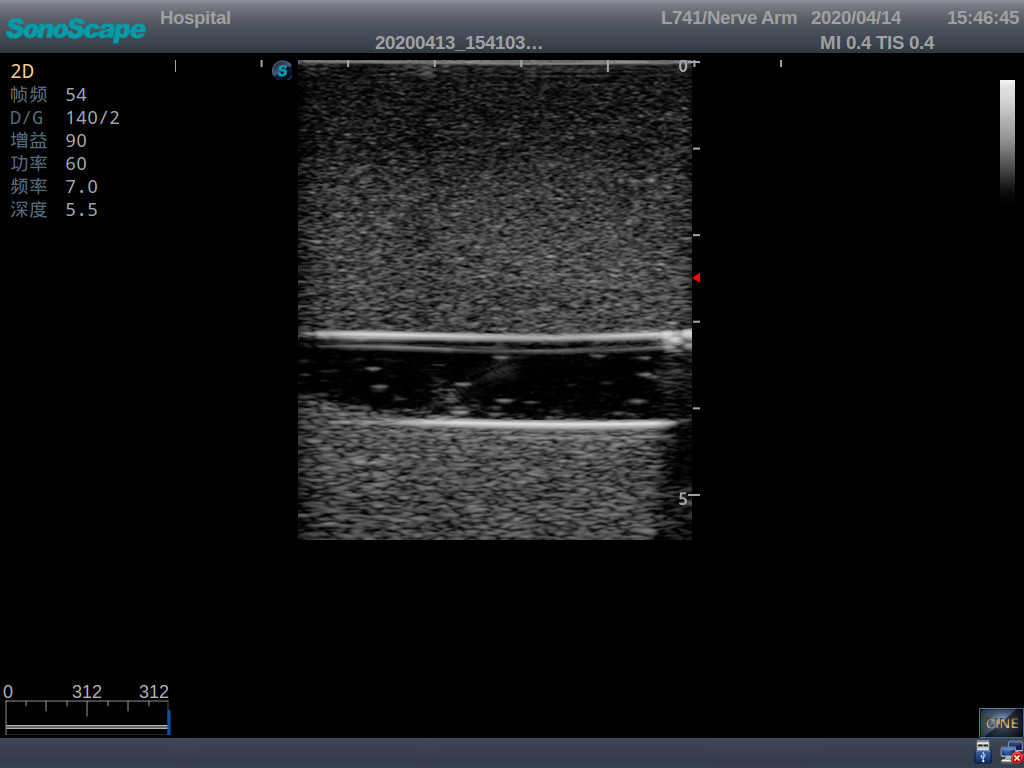

5)   Observe the guide wire marches

6)   Detect whether the catheter is properly placed